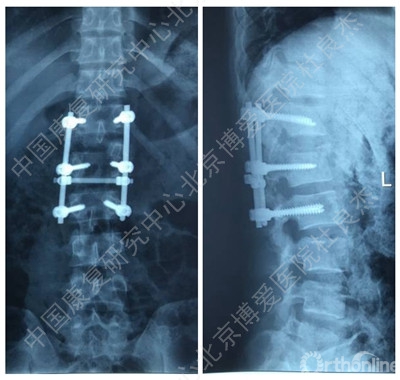

辅助检查

3、胸12椎弓根钉断裂

AO分型,C3型骨折,极度不稳。胸腰段骨折,根据Load–sharimg评分,大于7分,且伴有后方结构破坏,单纯的后路短节段固定稳定性肯定是不行的,内固定失效的可能性较大。建议后方长节段固定+前方植骨融合内固定。

胸腰段椎体骨折脱位出现断钉原因:1.此处骨折脱位除椎体骨折外,附件及韧带等软组织损伤严重。从解刨上看3种因素决定此处是应力集中地。需固定到伤椎上下各2个椎体。2.从影像学可知,胸12腰1似乎过度撑开了。3.从影像学可知,极度不稳,应融合胸12腰1。下一步:去除断钉,延长上方固定到胸10或11并做后路截骨椎间隙植骨。或前路椎间隙植骨融合内固定